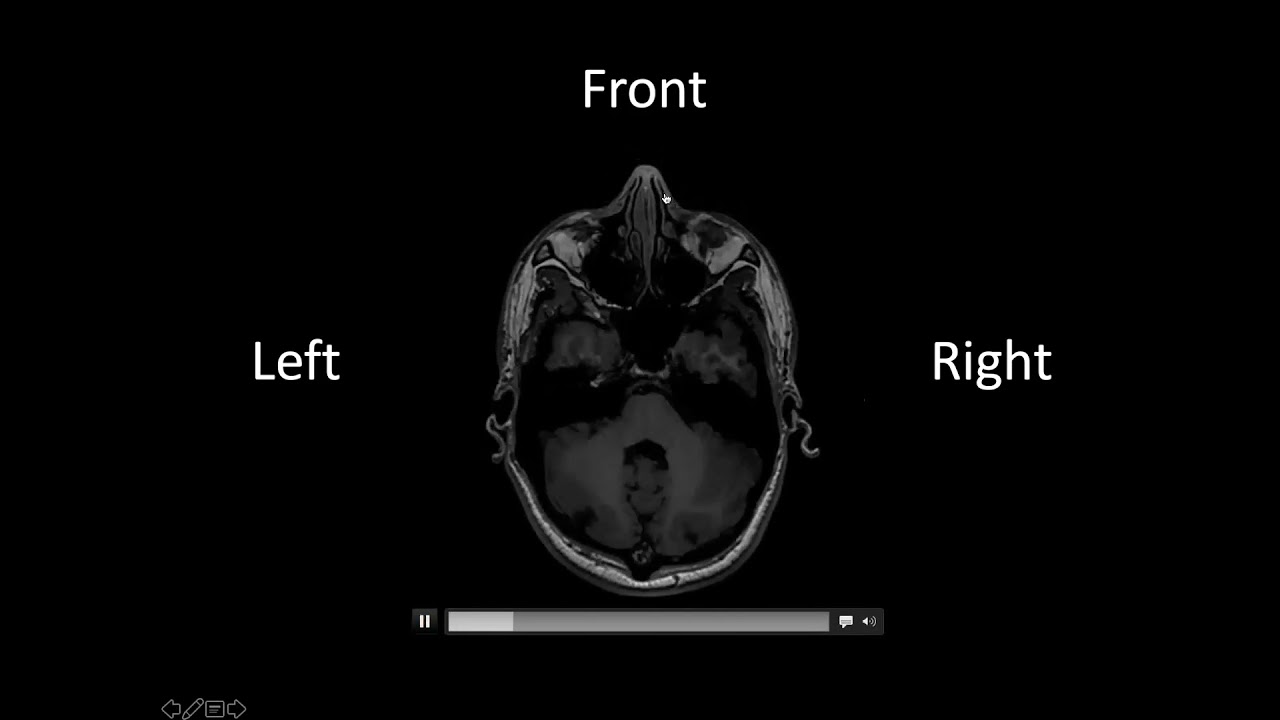

Digital Discovery: multiple sclerosis and the brain

Описание: Professor Anne La Flamme is a senior immunologist at the Malaghan Institute at Victoria University of Wellington, where she leads the multiple sclerosis (MS) research programme. Her research focusses on optimising current treatments and finding new drugs to improve the lives of people living with MS. Anne's extensive research career has spanned the University of Washington, Cornell University, and the Whitehead Biomedical Research Institute. Anne will be speaking about her research into MS, particularly around promoting remyelination with the drug nalfurafine which is commonly used to treat itching in patients with kidney failure.